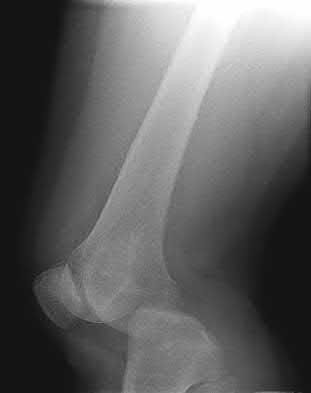

2. # A 35-year-old woman is involved in a head-on collision while driving. Initial radiographs are shown in Figures 8a and 8b. Injury to what vessel increases the risk for osteonecrosis of the injured bone?

5. Artery of the tarsal sinus Corrent answer: 4

The patient has a Hawkins type III talar neck fracture-dislocation with a risk of osteonecrosis ranging from 69% to 100%. Anatomic studies have shown that the artery of the tarsal canal supplies the lateral two thirds of the talar body.

The other vessels listed provide no significant contribution to the talus.